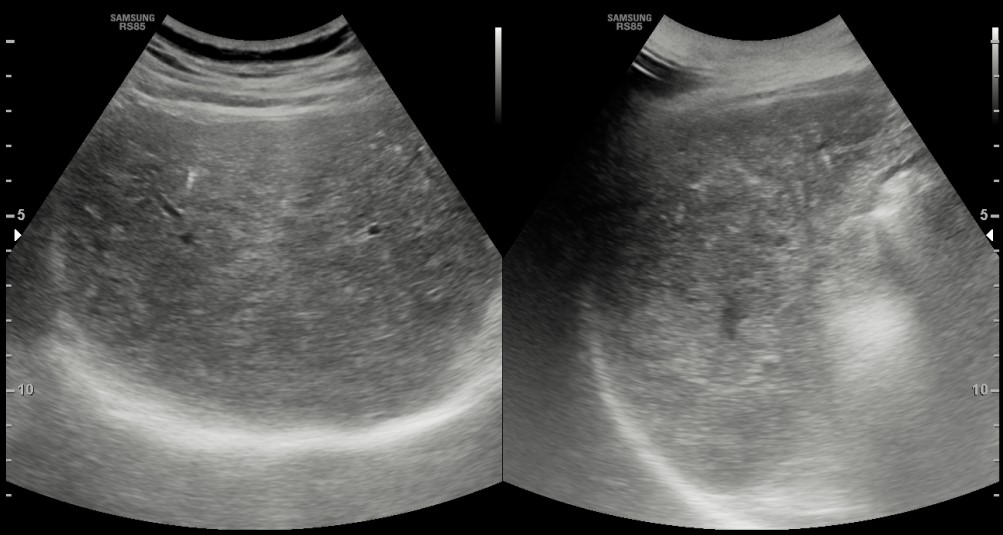

[366,Hepatobiliary [HB]] 62/M,Abnormal finding on upper abdominal ultrasonography during a health check-up

Hepatobiliary [HB]

US,

What is the most likely diagnosis?

Hepatic steatosis

Liver cirrhosis

Primary hemochromatosis

Biliary hamartomatosis

Budd-Chiari syndrome